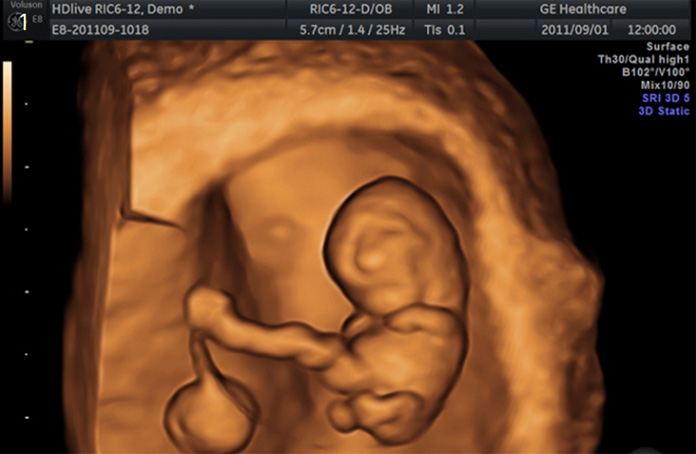

4D 입체영상초음파

입체영상초음파는 선택검사이며, 예약이 필요합니다. 태아의 얼굴, 손, 발, 척추 등이 가장 잘 보이는 임신 23-28주 사이에 실시하여 실물과 유사한 사진을 얻어 미리 아가를 만나볼 수 있는 검사입니다. 우리산부인과는 보다 감각 있는 사진을 위하여 초음파 "GE HD live "을 사용하고 있습니다.